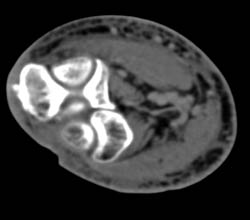

Diagnosis

Cellulitis Fluid